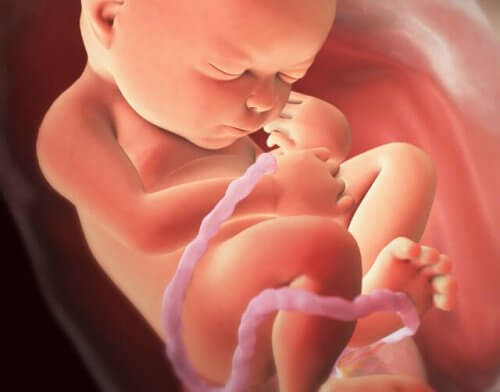

Se le denomina sufrimiento fetal o distress fetal a las alteraciones que se producen en el feto antes o durante el parto, de tal forma que inciden negativamente en su fisiología. Dichas alteraciones vienen a ser las lesiones que sufre el feto como consecuencia de las complicaciones que puedan surgir cuando el feto aún se encuentra dentro de la placenta.

Asimismo, este término también es utilizado para designar cualquier cambio en el bienestar del feto; que por lo general, suele ser falta de nutrientes u oxígeno (a través de la placenta) entre la madre y el feto.

La causa más común de sufrimiento fetal es la falta de oxígeno o bien porque el cordón umbilical está siendo comprimido o por otro tipo de complicaciones, como pueden ser las hemorragias.

- Problemas con el cordón umbilical, entre otros.

La insuficiencia fetal crónica se caracteriza por una insuficiencia placentaria progresiva, la cual provoca trastornos en el desarrollo del feto; es decir; un retardo en el crecimiento intrauterino y puede llevar al óbito fetal.